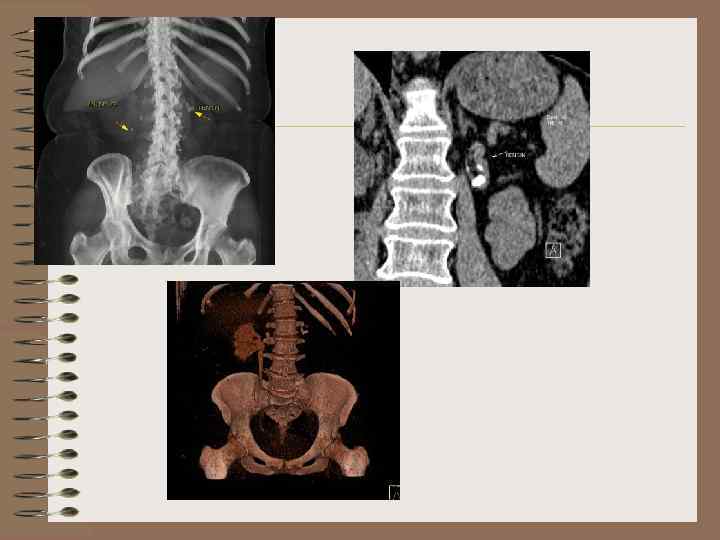

Аномалии расположения Дистопии • Гомолатеральная • Гетеролатеральная

Гомолатеральные дистопии • Тазовая • Подвздошная • Поясничная

• Необычное расположение почки (по отношению к позвонкам) • Абсолютный признак дистопии –короткий мочеточник • Низкий уровень отхождения почечных артерий. В норме на уровне L 1 • Необычный поворот почки (направление лоханки и чаш) • Добавочные аномальные артерии • Ограничение подвижности

Тазовая дистопия • Тень ЧЛС расположена в тазу • Лоханка маленькая, ориентирована кпереди • Мочеточник короткий, отходит от латеральной либо передней поверхности • Сосуды отходят на уровне бифуркации, либо от подвздошных сосудов

ВУ, КТ – тазовая дистопия

Тазовая дистопия

Тазовая дистопия. Беременность лоханка

Подвздошная дистопия Почка располагается на уровне входа в таз

Поясничная дистопия • Почка расположена ниже обычного • Лоханка ориентирована латерально, по передней поверхности • Короткий мочеточник

Поясничная дистопия Поворот лоханкой кпереди

Поясничная дистопия